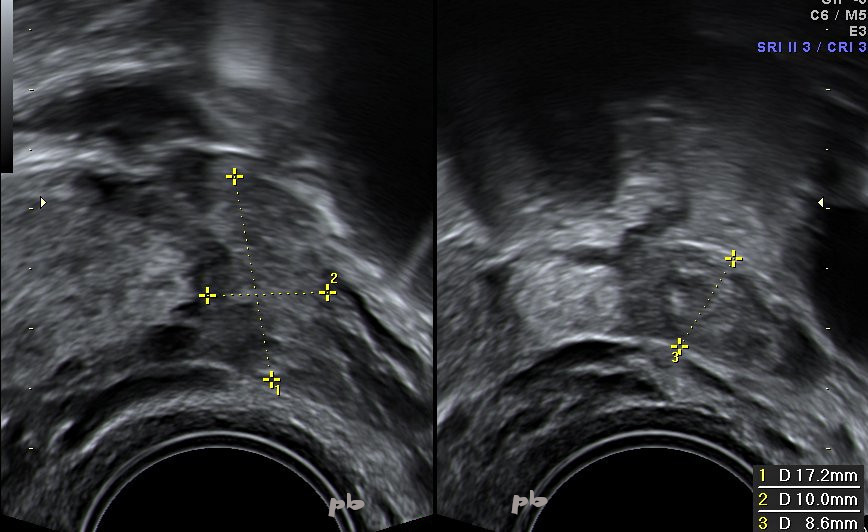

23- Ectopic Pregnancy + Intrauterine Pregnancy (same patient as 22)

The ectopic pregnancy (between crosses) measures 11 mm, adjacent to the left ovary. ‘Target’ image with a hyperechoic center. The outer layer corresponds to the tubal wall.